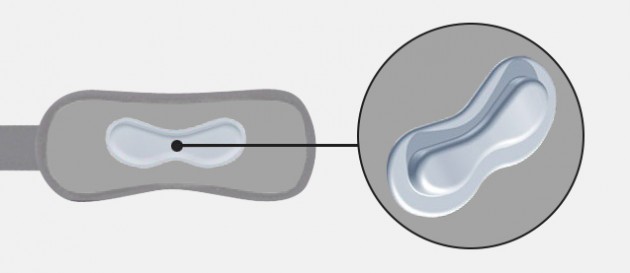

Orteza podrzepkowa EB-P/RZ została wykonana z najlepszych materiałów. Odciąża ona przyczep końcowy mięśnia czworogłowego uda, niwelując tym samym jego wzmożone napięcie. Dzięki temu, stabilizuje i odciąża rzepkę, zapobiegając bólom w stawie rzepkowo-udowym oraz jej degeneracji. Do ortezy zamontowano pelotę silikonową o anatomicznym kształcie, która doskonale obejmuje więzadło rzepki, a jej półsztywna konstrukcja zapewnia prawidłowe odciążenie. Zastosowany anatomiczny kształt peloty zapobiega również zsuwaniu się ortezy w trakcie wysiłku fizycznego. Dodatkowo zainstalowano taśmę obwodową zakończoną plastikową klamerką, pozwalającą na mocne i trwałe zamontowanie wyrobu na kończynie. Wyrób wykonany z surowca AirDistance II™ oraz Sanmed II™.